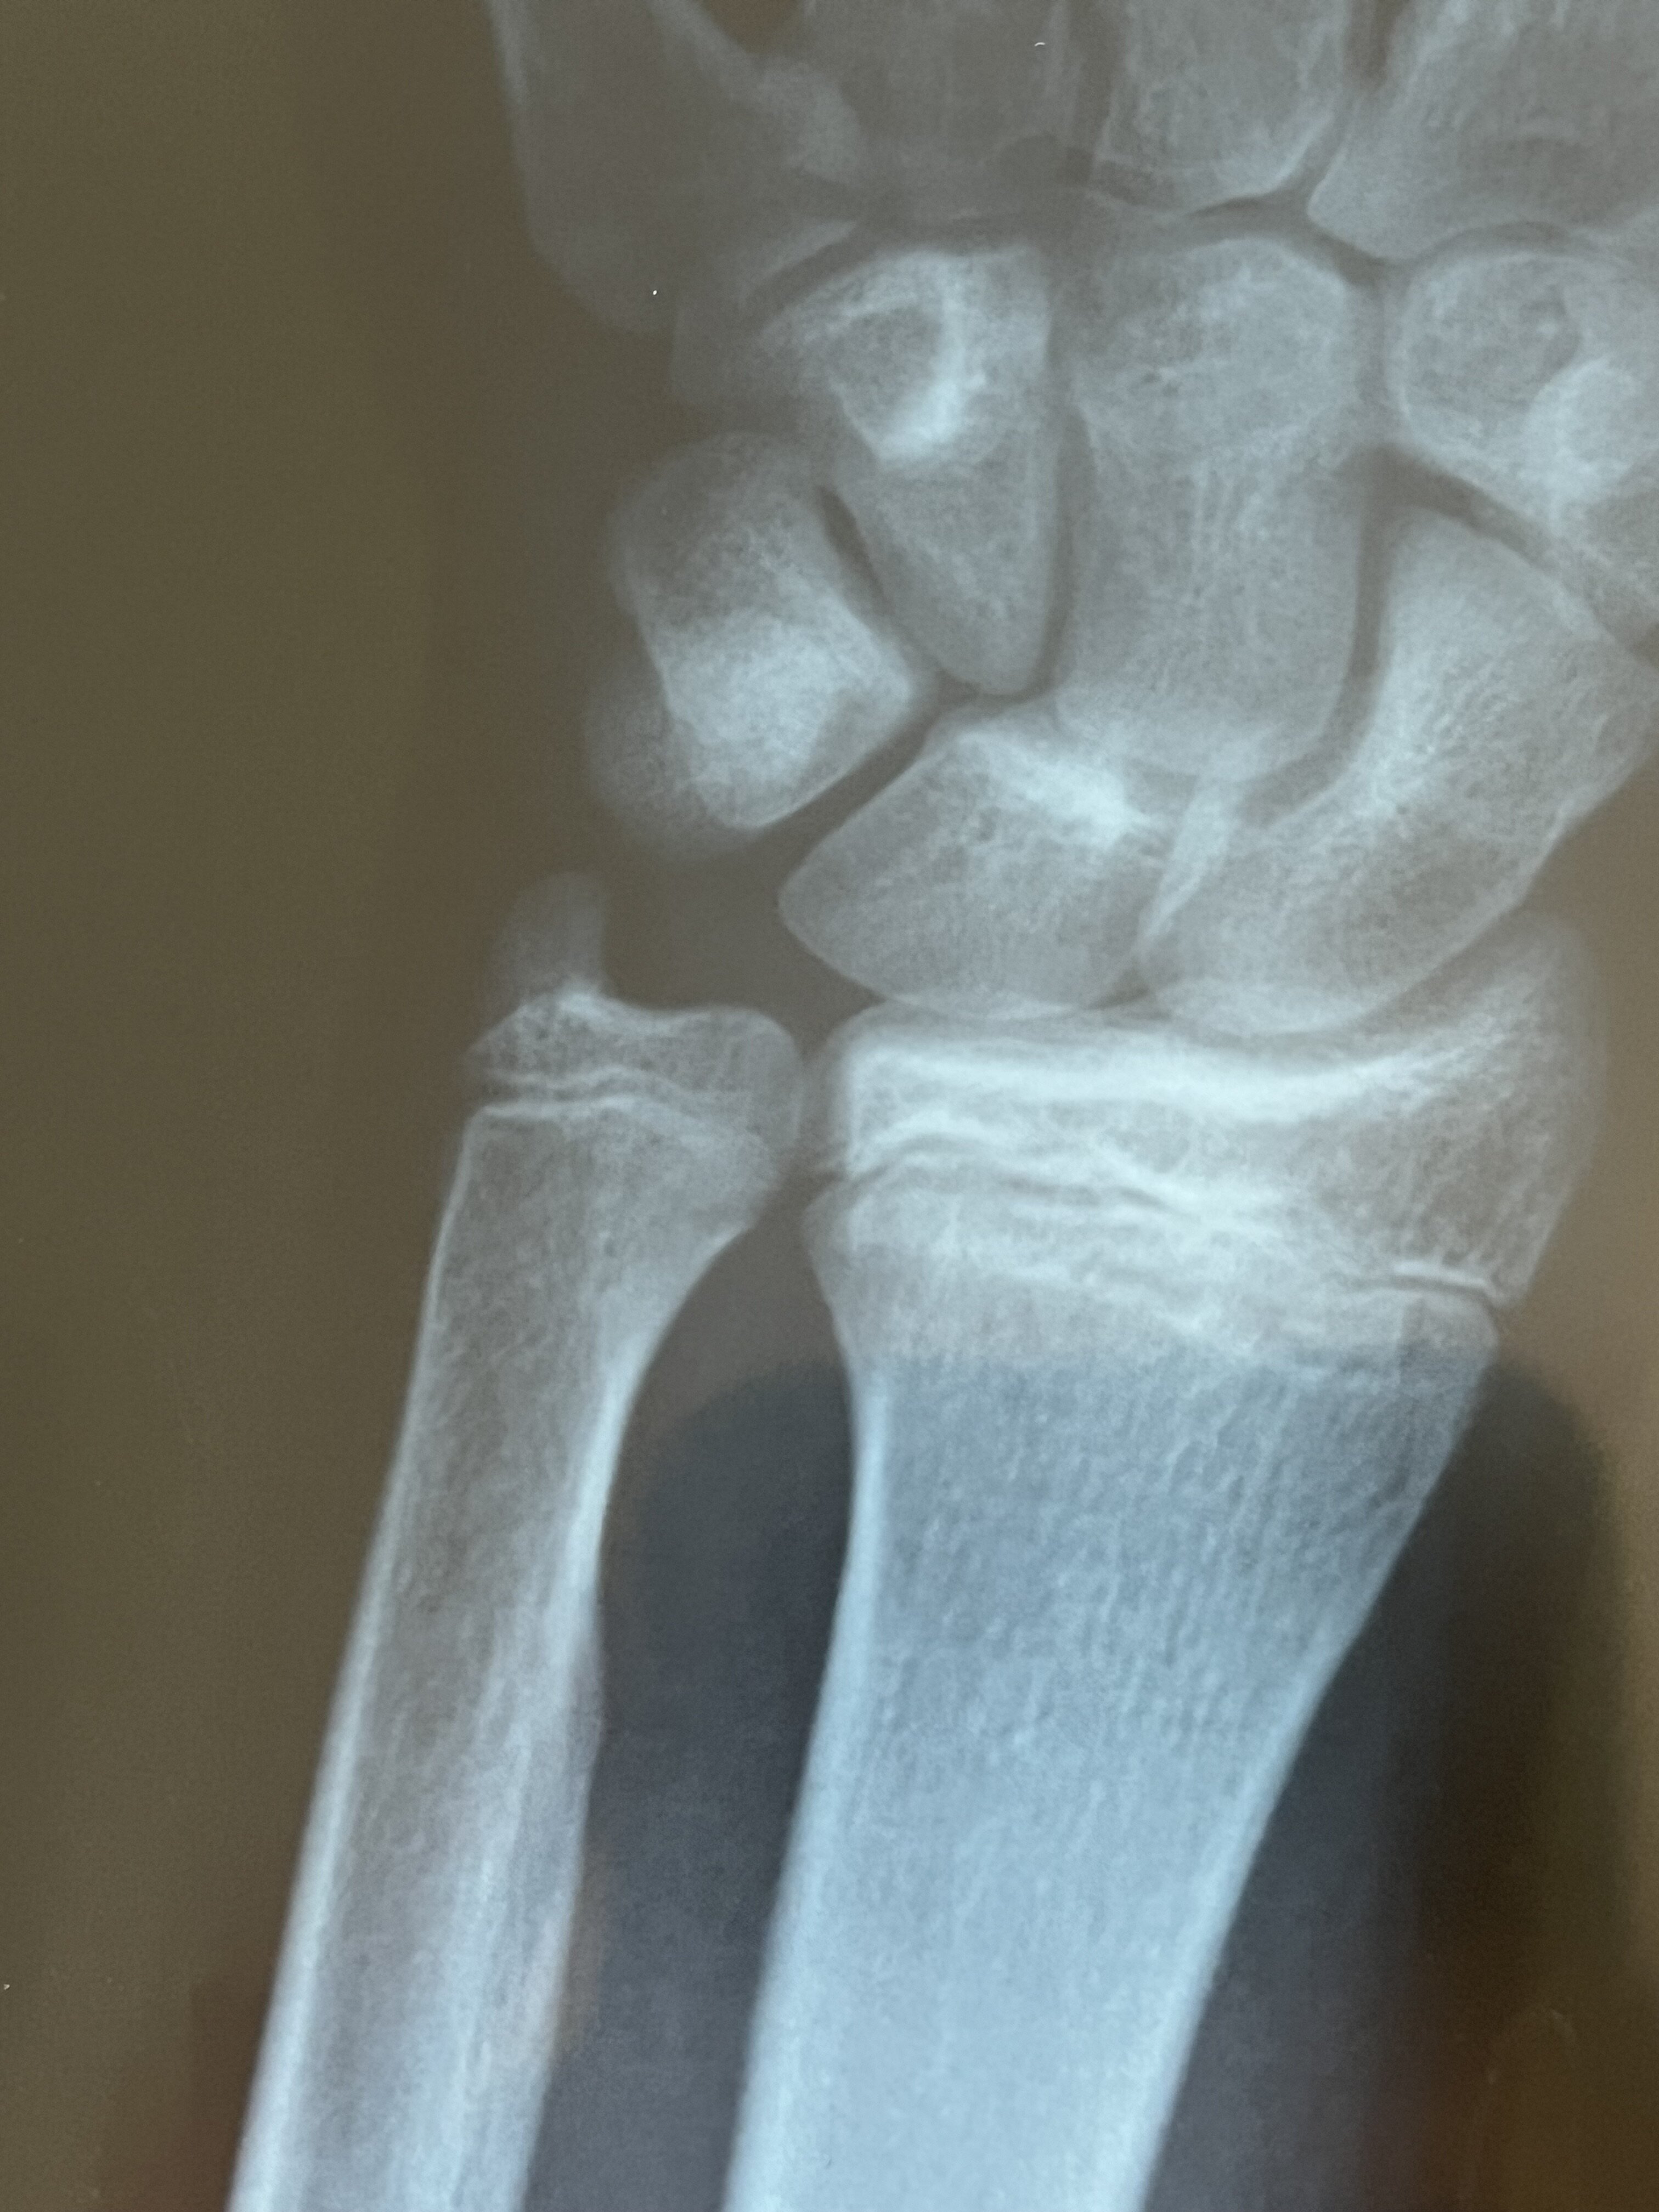

Hahahaha jfl if that would be true all the martyrs wouldn’t have endured being tortured and just jumped the day before the torture. I think I won’t jump but yeah I’m kinda cooked. But I know jfl my dream height would be 175 cm but 6 months ago my plates alr looked like this

IMG 4104